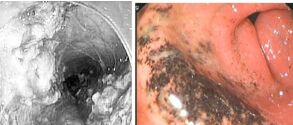

1、胃镜检查:胃镜检查是诊断消化性溃疡的主要方法,其不仅可对胃乃至十二指肠黏膜直接观察、摄像,还可在直视下取活组织作病理学检查及幽门螺杆菌检测,因此对溃疡的诊断具有十分重要的意义。

3、鉴别诊断:当胃镜检查发现胃溃疡时,诊断似乎非常明确,但是还应注意与引起胃溃疡的少见特殊病因或以溃疡为主要 表现的消化道肿瘤鉴别。胃的巨大溃疡在内镜上与胃恶性肿瘤的鉴别亦有一定的困难,而且有些溃疡与早期癌区别极为困难,故目前临床上行胃镜检查时若发现胃部 的溃疡,临床医师通常会取活组织行病理检查,并且要求患者治疗后复查并多次取活组织行病理检查,以防病检出现假阴性。